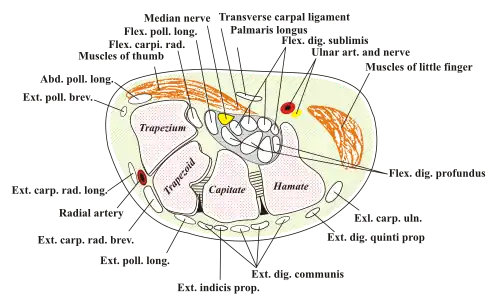

Kanał nadgarstka (łac. canalis carpi) – kostno-włóknisty kanał utworzony przez kości nadgarstka i część dalszą[1] troczka zginaczy[2].

Zawiera nerw pośrodkowy i dwie pochewki maziowe: leżącą bardziej bocznie pochewkę promieniową ścięgna mięśnia zginacza kciuka długiego i przyśrodkowo łokciową dla 8 ścięgien mięśni zginaczy palców (zginaczy powierzchownych i zginaczy głębokich)[2].

Jego ograniczeniami są:

- promieniowo – wyniosłość promieniowa nadgarstka (łac. eminentia carpi radialis) utworzona przez guzek kości łódeczkowatej i guzek kości czworobocznej większej,

- łokciowo – wyniosłość łokciowa nadgarstka (łac. eminentia carpi ulnaris) na którą składa się haczyk kości haczykowatej i kość grochowata,

- od strony grzbietowej – kości nadgarstka leżące między wyniosłościami i ich więzadła[3],

- od strony dłoniowej – troczek zginaczy nadgarstka[4].